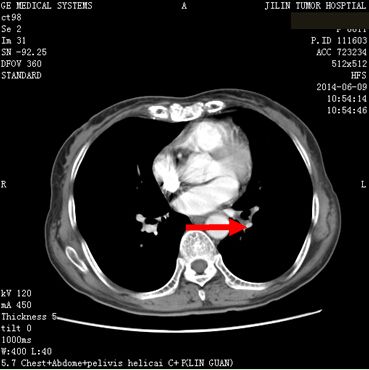

患者任某,女,60岁,患者因刺激性咳嗽3个月,右上腹部疼痛2个月于2014年4月11日就诊。入院后行肺增强CT、全腹增强CT;:左肺下叶支气管开口周围见类圆形肿块影,大小约为4.75×4.54cm,肿块包绕左肺下静脉及左肺下动脉干,肿块不均匀强化,左肺下叶支气管开口截断,左肺下叶内前基底段肺组织实变。左肺门见肿大淋巴结与肺门肿块融合。肝脏大小及形态未见确切异常,肝实质内弥漫性分布低密度肿块影,肿块融合成团,约占据整个肝脏,增强检查环形强化,选择病灶2.81×2.68cm,腹腔内见多个肿大淋巴结,融合成团,包绕邻近组织,较大约为3.21×2.57cm,左侧肾上腺见类圆形肿块影,大小约为2.49×1.99cm,增强检查略强化。明确诊断为:左肺下叶小细胞肺癌(T2aN1M1b)Ⅳ期,广泛期、左肺门淋巴结转移、 多发肝转移、腹腔淋巴结转移。符合我院正在进行的Ipilimumab联合EP治疗广泛期小细胞肺癌的III期临床研究,给予入组。于2014年5月1日开始给予EP方案化疗(VP-16,100mg/m2,157mg,d1-3;DDP,75mg/m2,118mg,d1),共给予化疗4周期,第3周期开始给予加用Ipilimumab单抗(10mg/kg),现患者已应用2周期,无明显严重不良反应发生。2周期后疗效判定:靶病灶1、左肺内病灶消失,2、左肾上腺转移病灶11.6×9.5=110.2,3、肝转移病灶11.3×9.1=102.83。靶病灶乘积之和213.03,疗效判定PR,非靶病灶:1、肝内其他转移病灶,存在,2、腹腔其他转移淋巴结,存在,疗效判定SD,总体疗效判定PR。现患者仍在继续用药中。

2014年6月9日 治疗后